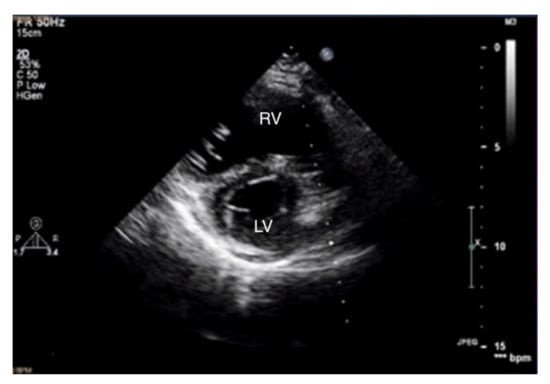

Transthoracic echocardiography (TTE) in a patient with advanced PAH is conspicuous by the RV cavity′s abnormal shape, especially in the parasternal short axis (Figure 5). The RV assumes a spherical shape, and the interventricular septum protrudes into the LV, forming the so-called D-shape sign [18]. If a D-shaped LV appears in the end-diastolic phase, it suggests RV pressure overload, whereas a D-sign shape in diastole suggests RV volume overload [19,20].

Figure 5.

D-sign, enlarged right ventricle, ventricular septum displaced towards LV. 2D-TTE, short-axis view (SAX). LV: left ventricle; 2D-TTE: two-dimensional transthoracic echocardiography.